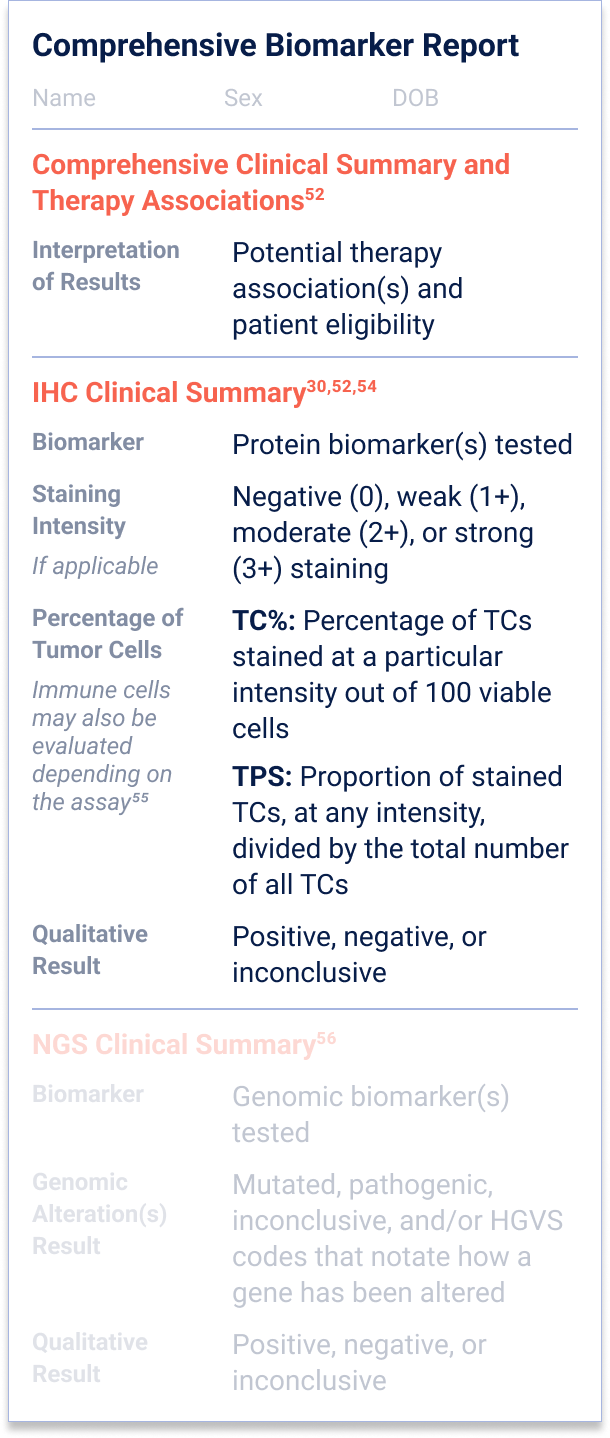

52. Penault-Llorca F, et al.

Virchows Arch. 2022;481(3):351-366.

54. Baskovich B, et al.

Arch Pathol Lab Med. 2024;148(10)1105-1109.

55. Mayo Clinic Laboratories. PD-L1 Testing by Immunohistochemistry. Accessed November 20, 2025.

https://news.mayocliniclabs.com/2022/08/22/pd-l1-testing-by-immunohistochemistry/.

56. Schmid S, et al.

ESMO Open. 2022;7(5):100570.